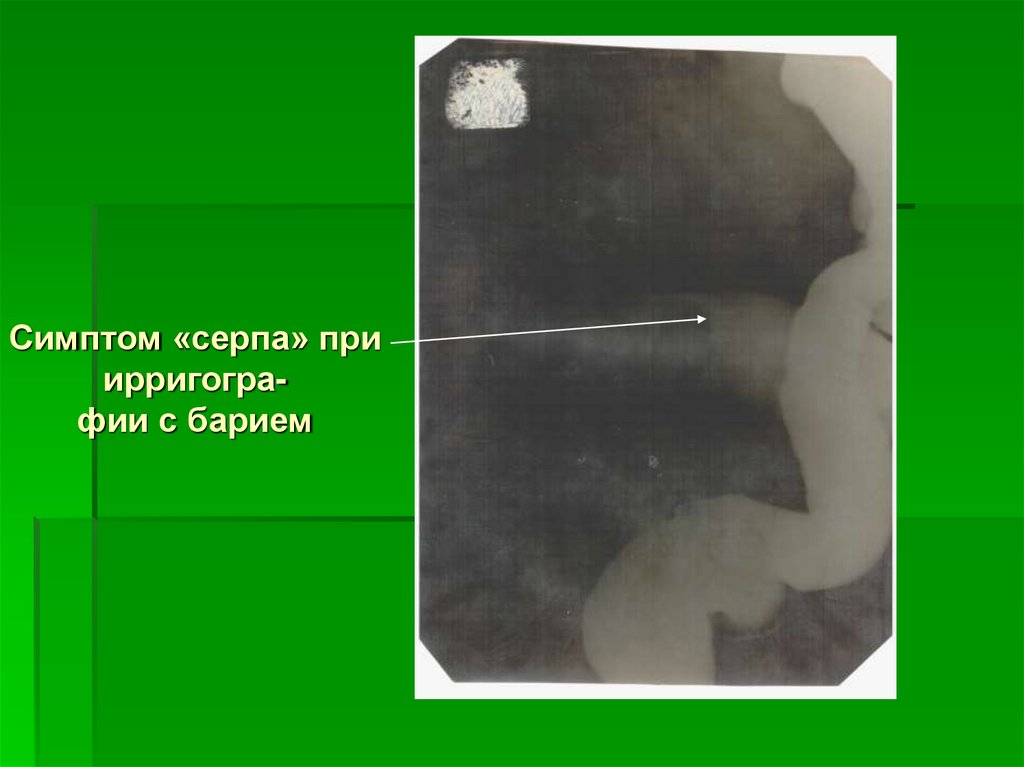

65. Симптом «серпа» при ирригогра- фии

Симптом

«серпа» при

ирригографии

Симптом «серпа» при

ирригографии с барием